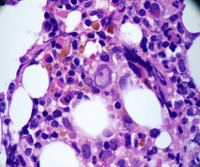

Marrow biopsy with pronormoblast showing a parvovirus inclusion.